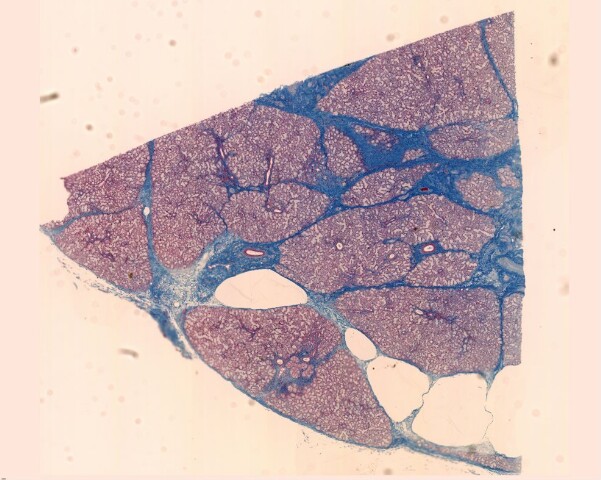

Ghiandola salivare sottolinguale. Colorazione: Azan-Mallory

Sezione di una ghiandola salivare sottolinguale.